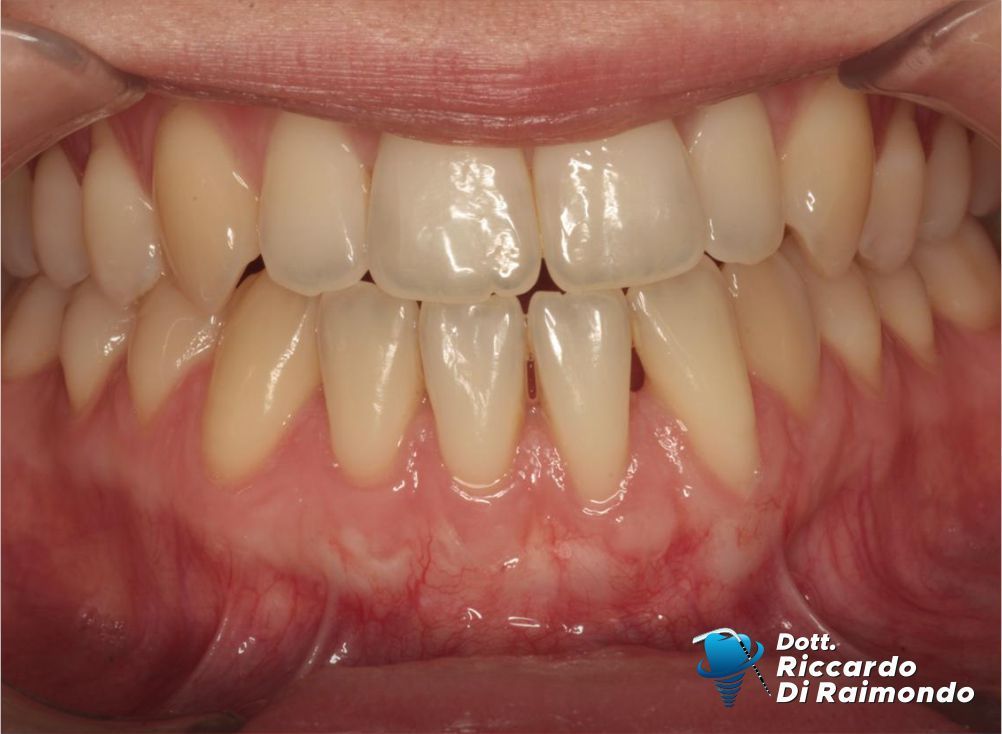

Considerate queste condizioni, ho pianificato un intervento di chirurgia plastica parodontale (chirurgia mucogengivale) con l’obiettivo di ottenere la copertura radicolare e, allo stesso tempo, migliorare la qualità e lo spessore dei tessuti gengivali, aumentando la stabilità biologica nel lungo periodo.

La procedura chirurgica ha previsto il prelievo di un innesto di tessuto connettivo dal palato, successivamente utilizzato per aumentare lo spessore dei tessuti nell’area interessata. La copertura delle recessioni è stata quindi eseguita mediante una tecnica di avanzamento coronale modificato, particolarmente indicata nel trattamento delle recessioni multiple.

Questo approccio consente non solo di ottenere un miglioramento estetico significativo, ma soprattutto di modificare il fenotipo gengivale, creando condizioni biologiche più favorevoli alla stabilità dei tessuti nel tempo.

Fine Trattamento